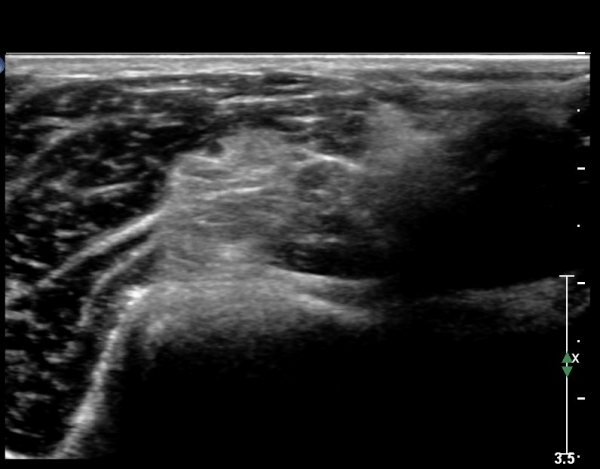

ÃÊÀ½ÆÄ ¼Ò°ß ÆÈ²ÞÄ¡ ¾Õ Ȳ´Ü¸é °Ë»ç¿¡¼ ¼ÒµÎ Àü¸é¿¡ ÀÌÁú¼º °í¿¡ÄÚ(heterogenous htperechoic)ÀÇ Á¾±«(mass)°¡ Èİñ°£½Å°æÀ» Ç¥ÃþÀ¸·Î ÀüÀ§½ÃŰ´Â ¾ç»óÀ¸·Î °üÂûµÊ(»çÁø 1).